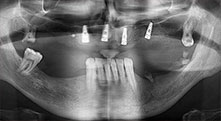

Restbezahnung

Ein 40-jähriger Patient mit desolater Restbezahnung wünscht eine Implantatversorgung. Da er Raucher ist, wird im Oberkiefer kein Sinuslift mit festem Zahnersatz, sondern eine Stegprothese auf vier anterioren Implantaten geplant.

Implantate

Die vier Implantate befinden sich wie geplant in situ. Die distalen Oberkiefermolaren dienen noch zur Fixierung der unterfütterten Prothese, die einen Monat nach Implantation eingegliedert wird.